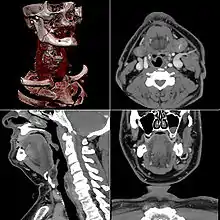

Computed tomography

Computed tomography or CT scan (previously known as CAT scan, the "A" standing for "axial") uses ionizing radiation (x-ray radiation) in conjunction with a computer to create images of both soft and hard tissues. These images look as though the patient was sliced like bread (thus, "tomography" – "tomo" means "slice"). Though CT uses a higher amount of ionizing x-radiation than diagnostic x-rays (both utilising X-ray radiation), with advances in technology, levels of CT radiation dose and scan times have reduced.[1] CT exams are generally short, most lasting only as long as a breath-hold, Contrast agents are also often used, depending on the tissues needing to be seen. Radiographers perform these examinations, sometimes in conjunction with a radiologist (for instance, when a radiologist performs a CT-guided biopsy).